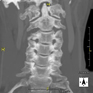

Prova radiològica que consisteix en obtenir imatges de les cervicals vertebrals d'alta definició anatòmica, mitjançant l'ús d'un equip de TC (Tomografia Computeritzada). Indicacions: cervicàlgia amb/ sense irradiació a braços, traumatisme.

Prova radiològica que consisteix en obtenir imatges de les vèrtebres cervicals d'alta definició anatòmica, mitjançant l'ús d'un equip de TC (Tomografia Computeritzada). Indicacions: dolor cervical amb/sense irradiació als braços, traumatisme, malformacions congènites. - TC Columna dorsal